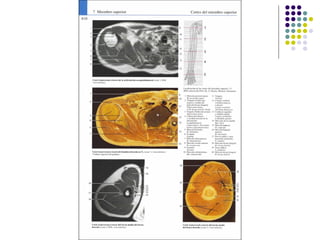

La extremidad superior humana incluye el hombro, el brazo, el codo, la muñeca y la mano. Está diseñada para una variedad de funciones motoras finas como agarrar objetos y realizar tareas manuales complejas. La coordinación precisa de los músculos y los huesos de la extremidad superior es clave para su versatilidad funcional.